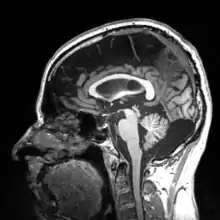

More recently, computed tomography has played a large role in reconstructing endocasts. The procedure is non-invasive and has the advantage of being able to analyze a fossil in record time with little risk of damaging the fossil under review. CT imaging is achieved through the application of x-rays to produce tomographs, or sectional density images, which are similar to the images produced during MRI scans.[8] CT scans use slices approximately 1 mm thick to reconstruct a virtual model of the specimen.[9] This method is especially useful when a fossil cranium is occupied by a natural endocast that cannot be removed without destroying the skeletal portions of the fossil. Because the cranium and its contents are of different densities, the endocranial cavity and its unique traits can be reconstructed virtually.[8]

Radiographic technique such as computed tomographic imaging, or CT scans, coupled with computer programming have been used to analyze brain endocasts from as early as 1906.[10] Recent development of advanced computer graphics technology have allowed scientists to more accurately analyze of brain endocasts. M. Vannier and G. Conroy of Washington University School of Medicine have developed a system that images and analyzes surface morphologies in 3D. Scientists are able to encode surface landmarks that allows them to analyze sulcal length, cortical asymmetries and volume.[11] Radiologist, paleoanthropologists, computer scientists in both the United States and Europe have collaborated to study such fossils using virtual techniques.[10]